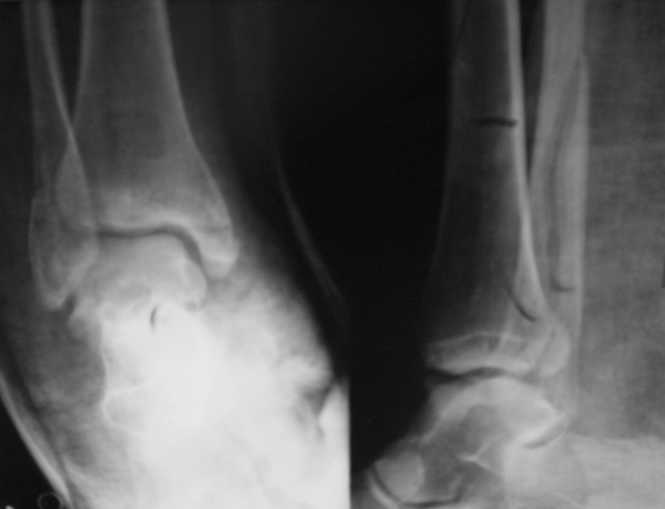

Ув. коллеги. Мы считаем, что синтезировать необходимо медиальную лодыжку, она ротирована. Малоберцовую кость лучше не трогать. Довольно травматично будет, фрагменты неплохо стоят. И то, оперировать медиальную лодыжку где-то в трехнедельном сроке, чтобы малоберцовую кость не развалить. Мнений много, мы благодарны за участие.

Мы считаем, что синтезировать необходимо > медиальную лодыжку, она ротирована.

"Мы" не понимаем такую трудную логику, обычно

фиксируют латеральную лодыжку, самый главный элемент в голеностопном суставе, и при восстановлении ориентируется на длину малоберцовой.

При смещении "таран идет, где малоберцовая"

и происходит подвывих сустава из-за мощных

латеральных связок.

Медиальная лодыжка не несет нагрузку и не

является стабилизатором сустава. При изолированных

переломах медиальной лодыжки и при отсутствии разрыва синдесмоза не происходит смещения

голеностопа медиально, и поэтому в некоторых случаях (изолированные и многооскольчатые) можно

игнорировать фиксацию медиальной.

Очень жаль, что Вы так считаете и не прислушались к мнениям уважаемых коллег. Проблема этого голеностопного сустава не в "висячей" внутренней лодыжки, а ротированной и, возможно, укороченной малоберцовой кости. На снимках подвывиха как-буд-то бы нет, но таран ротирован и это в дольнейшем будет причиной раннего артроза.